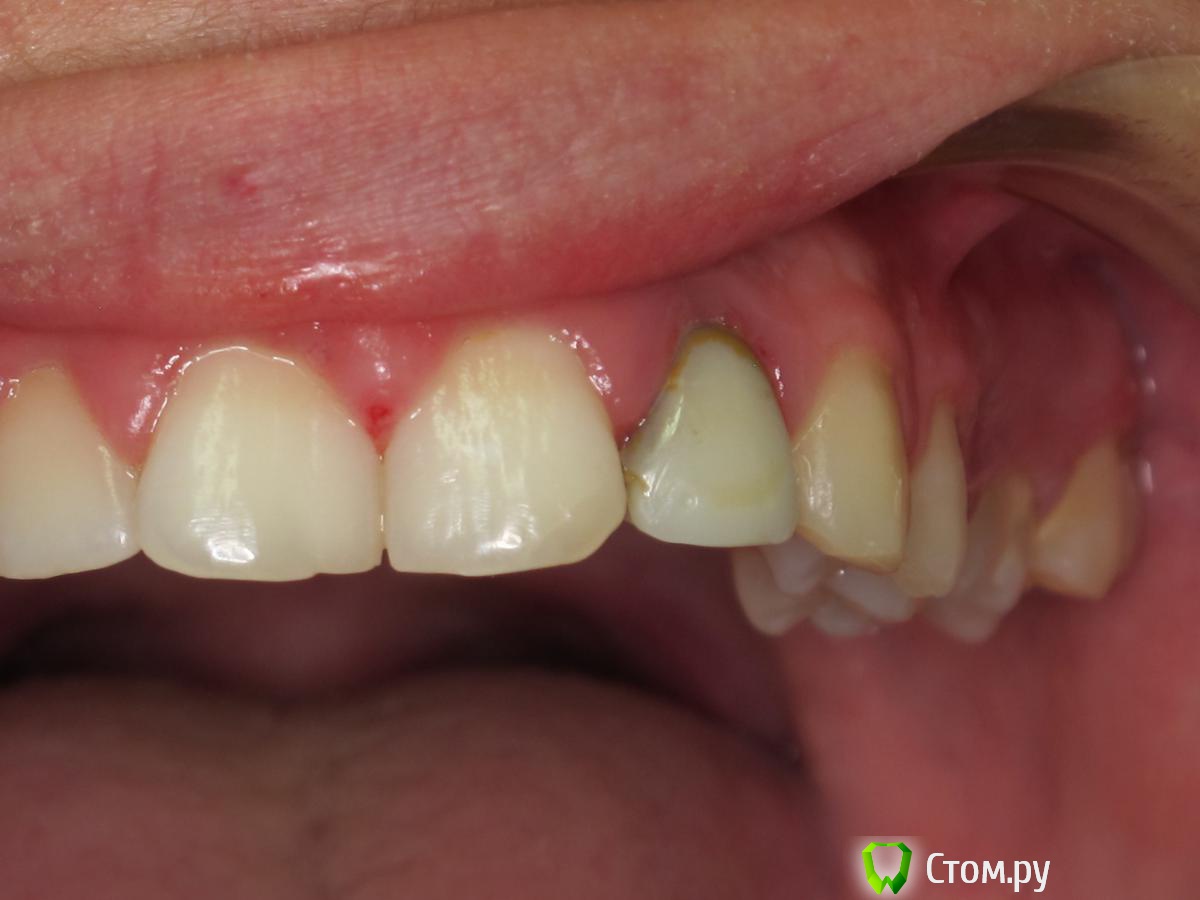

johniola Опубликовано 5 февраля, 2014 Поделиться Опубликовано 5 февраля, 2014 Девочка 19 лет из церковного приюта(иногда помогаю),22 зуб анкер+композит+хр периодонтитФото с свш +билд ап не нашёл,проостите Ссылка на комментарий

Bobby Опубликовано 6 февраля, 2014 Поделиться Опубликовано 6 февраля, 2014 Спасибо за публикацию. Видно что сделано, но не видно как. Все случаи индивидуальны и даже феррул-поддержка культевой части зуба будет иметь разные прогнозы у хрупкой молодой пациентки и мощного возрастного пациента. 2 Ссылка на комментарий